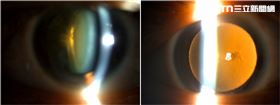

嬤看佛經變模糊 醫1招「開光」前途光明

73歲洪婦數十年來每天早晚虔誠誦經,但去年初她發現經...